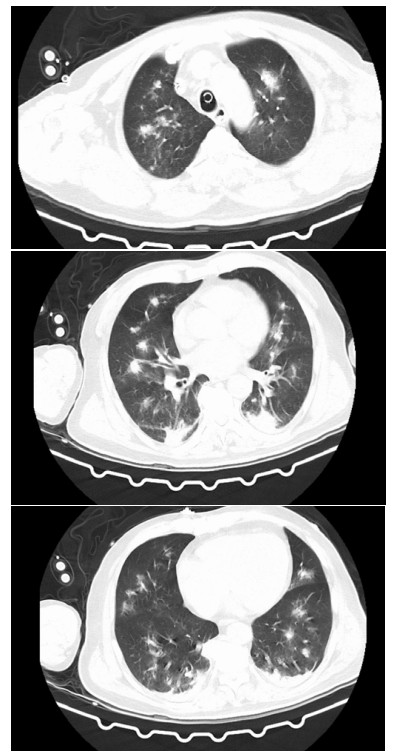

转入ICU后查体:神志模糊,躁动不安,偶有抽搐发作,呼吸急促,双肺可及湿罗音,立即予以气管插管接呼吸机辅助通气,镇痛镇静,头孢哌酮舒巴坦抗感染,继续予以利巴韦林抗病毒、免疫球蛋白应用以及保护脏器功能等对症治疗。2022-05-22患者布尼亚病毒核酸结果提示4.6×106 copies/mL,布尼亚抗体IgM阳性,相关化验提示:白细胞4.4×109/L,中性粒细胞绝对值3.03×109/L,血红蛋白141 g/L,血小板52×109/L,肌酐190 μmol/L,动脉血气pH 7.264,PO2 51.2 mmHg(1 mmHg=0.133 kPa),BE -8.3 mmol/L。床边胸片提示双肺炎症(见图 1),呼吸机支持参数较高,2022-05-23行床边气管镜检查(见图 2),气管内可见大量灰白色浓稠痰液,可见拉丝,予以充分抽吸并送检肺泡灌洗液,送检血G试验600 pg/mL,GM试验1.01 pg/mL,考虑重症肺炎,真菌感染可能,美国西弗吉尼亚大学医院深部真菌感染危险因素评分31分,予以调整抗感染方案为美罗培南联合伏立康唑抗感染治疗。2022-05-24患者肌酐持续升高,无尿伴代谢性酸中毒,予以行床边CRRT治疗。2022-05-27患者痰培养及肺泡灌洗液提示焦曲霉,进行CT检查,提示双肺异常密度(见图 3),予以调整抗感染治疗方案为头孢哌酮舒巴坦、伏立康唑、卡泊芬净抗感染治疗。经治疗后患者氧和指数稍好转,血小板计数较前升高(见图 4),2022-05-31患者家属因经济问题要求出院,1月后随访患者死亡。本研究通过医院伦理委员会批准(审批号:YX2022-041)。

图 3 2022-05-27胸部CT检查